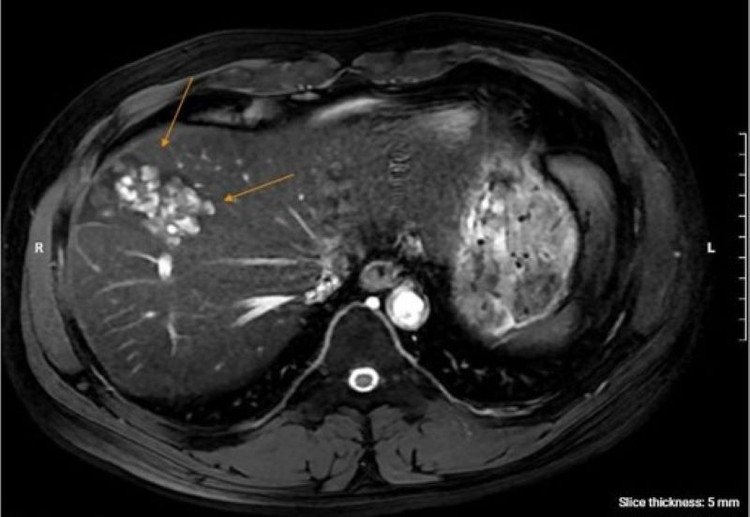

Để làm rõ chẩn đoán, bác sĩ chỉ định anh N. chụp cộng hưởng từ (MRI) ổ bụng, kết quả phát hiện nhiều ổ tổn thương khu trú gan phải, dạng hoại tử dịch hóa nhiều ổ, nghi ngờ do ký sinh trùng. Đồng thời, xét nghiệm chuyên sâu xác nhận dương tính với sán lá gan lớn và giun lươn.

Kết quả chụp cộng hưởng từ của bệnh nhân phát hiện nhiều ổ tổn thương khu trú gan phải/Ảnh medlatec.vn